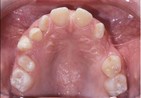

Photographs

side front front smile

Lateral Portrait Frontal Portrait Frontal Portrait Smile

front view left buccal maxillary mandibular

Right Buccal View Frontal View Left Buccal View Maxillary View Mandibular View